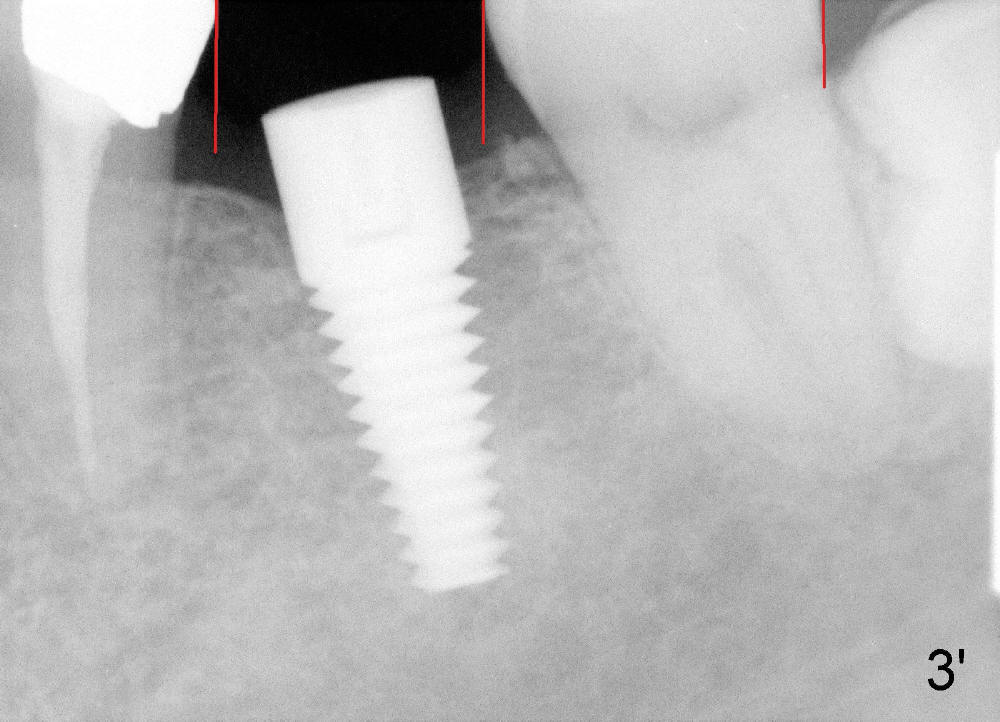

图三’:一般第一磨牙比第二宽(近远中,红线之间),但是这个病例,正好相反,说明第一磨牙缺失许久,邻牙向缺牙倾斜,移位。

分析这张X光片,告诉病人植牙修复有困难,但是却没有想像到那个具体问题,能猜到